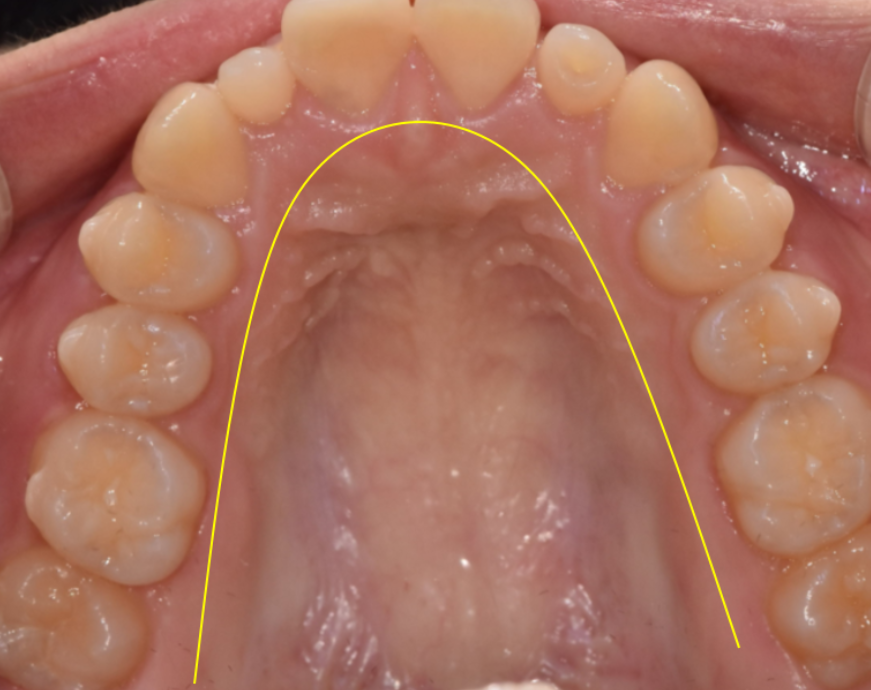

교정을 통해 전체 치열을 가지런하게 정리하여

보철 치료가 들어갈 수 있는 기초 작업을 완성해야합니다.

교정으로 공간이 만들어지면

그때 왜소치 크기를 정상치와 비슷하게 맞추어 줍니다.

땅을 고르고 울타리를 맞추는 교정

건물을 세우는 보철

때로는 둘이 함께해야

결과물이 완성될 수 있습니다.

교정만 했을 때는

여전히 옆니가 작아 아쉬울 수 있지만

보철까지 하면 완전히 달라져 보일 수 있습니다.